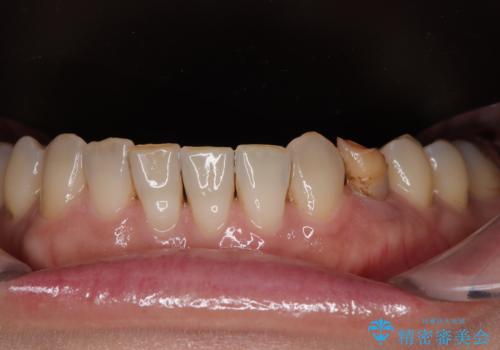

治療は計画通りに進み、約3か月で最終補綴まで完了。

見た目だけでなく、しっかり噛める機能も回復し、患者様にも大変ご満足いただけました。